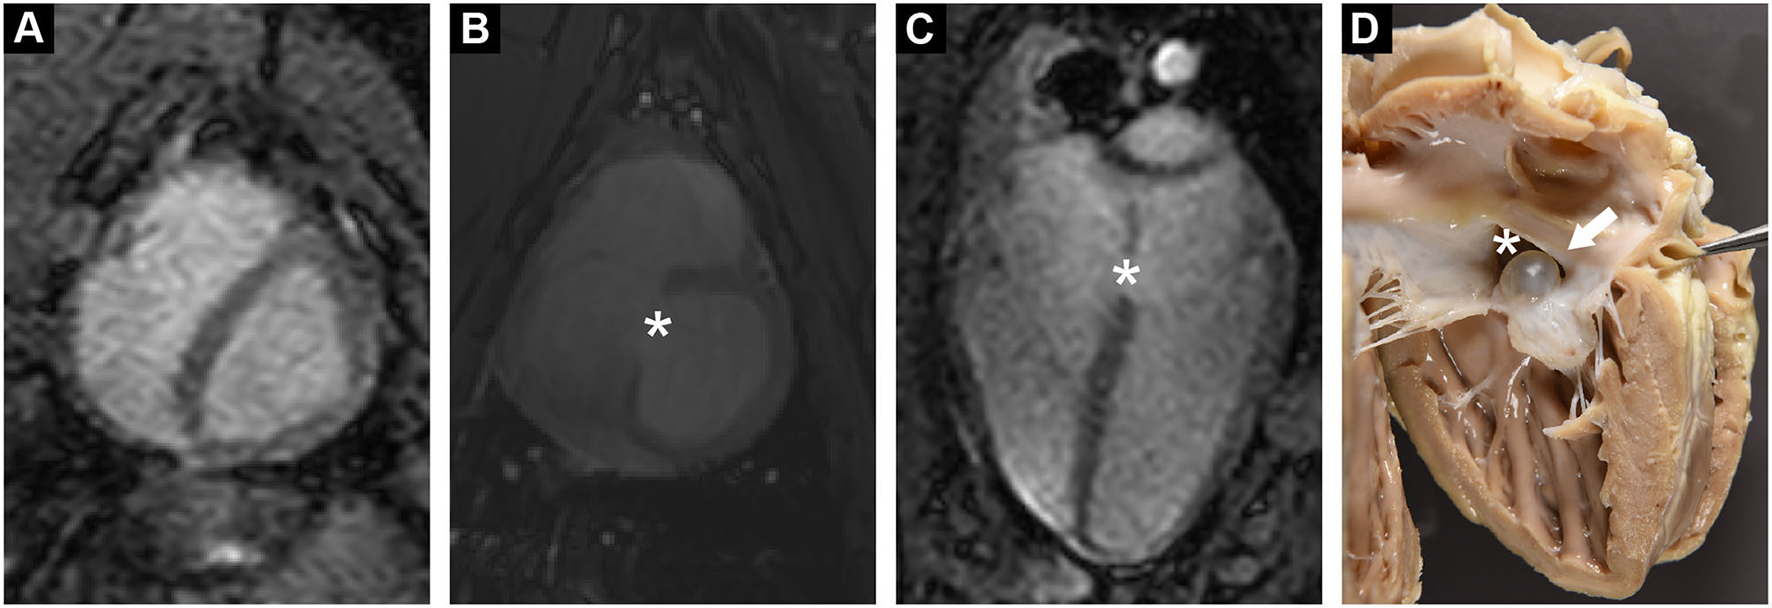

Functional MRI showed a clear defect in the atrial septum and a moderately enlarged right ventricle (Figures 1A–C). Analysis of the phase contrast MRI data performed on specialized GTFlow software (Gyrotools) revealed a diastolic L-R and a systolic right-to-left (R-L) shunt through the atrial septal defect, as well as mitral and tricuspid valve insufficiency and disturbed diastolic intra cardiac blood flow patterns. The systolic R-L shunt was discrete and had a total volume of 4.6 mL per stroke with a maximum jet velocity of 25 cm/s. Peak diastolic L-R shunt velocity through the ASD was 48 cm/s and the total volume of shunted blood was 14.1 mL per stroke. Peak velocities of mitral and tricuspid regurgitant jets were 36.4 and 46.9 cm/s, respectively, indicating a severe dysfunction of the atrioventricular (AV) valves (Figure 2). Surprisingly, mitral back-flow (regurgitation) was observed both during systole and diastole, with a total regurgitant volume of 15 mL per stroke (990 mL/min). Moreover, end-diastolic D-shape of the left ventricle was observed, indicating right ventricular volume overload (Figure 1A). Using blood particle tracking analysis, we were able to estimate that 26% of the blood volume contained in the diastolic mitral regurgitation (MR) jet directly crossed the ASD orifice and reached the RV, while only 18% of the systolic MR jet volume crossed the ASD in the subsequent diastole. Tricuspid regurgitation was limited to systole only, but was more severe with a total regurgitant volume of 22 mL per stroke (1.4 L/min).

Figure 1

(A) Functional cardiac MRI in short axis revealed a diastolic D-shaped left ventricle, indicating increased right ventricular pressure. (B,C) Cardiac MRI in short and long axis demonstrated a tissue defect in the inter-atrial septum (*). (D) Post mortem examination confirmed a large ASD (*). ASD was partially occluded by a serous cyst (arrow).